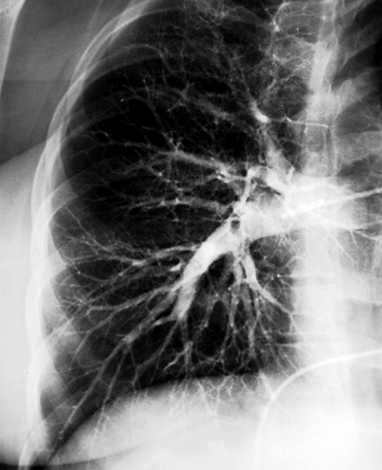

Figure 3: Pulmonary angiogram

Pulmonary angiography demonstrated an oblong filling defect within the interlobar branch of the right pulmonry artery. This defect extended into the middle lobe as well as a proximal segment of the right lower lobe.